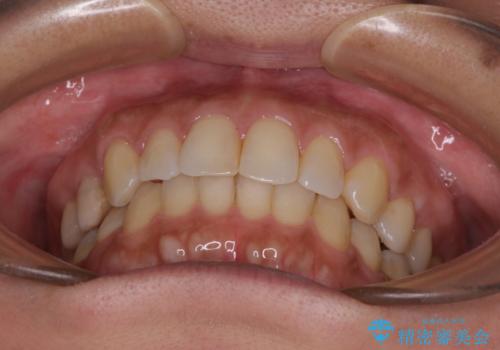

沖縄から飛行機で通院 インビザラインによる矯正治療

- 30代女性

- インビザライン

- 3年8ヶ月

- 定期的に東京に来るので、沖縄から矯正治療で通院したいとのことで来院された患者様です。

歯列不正は軽度であったので、応急処置の少ないインビザラインにて矯正治療を行うこととしました。